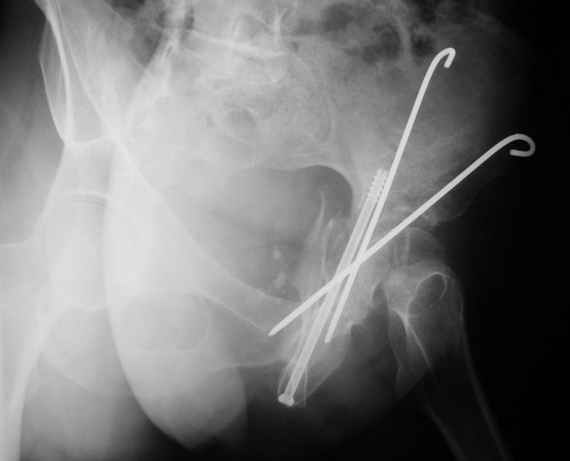

Женя! Класный перелом. Отлично репонируется изнутри таза, но лучше фиксированть сзади. Классический перелом для двустороннего доступа.

Однако есть альтернатива. Репозиция из подвздошного доступа тазовыми щипцами с разнодлинными браншами или тазовым пистолетом, а фиксация задней колонны через седалищный бугор или тазрвыми винтами 4,5 или каннюлированными 6,5 или 7,3. По-моему я посылал на ортофорум такой снимок, когда жаловался на ишемический неврит седалищного нерва через сутки после операции. Не забудь про шейку бедра - мне кажется будет хорош длинный PFN любой фирмы, какую ты найдешь, а нет так UFN + miss a nail, как это здорово делают мои земляки - Ебурбуки. Пока.